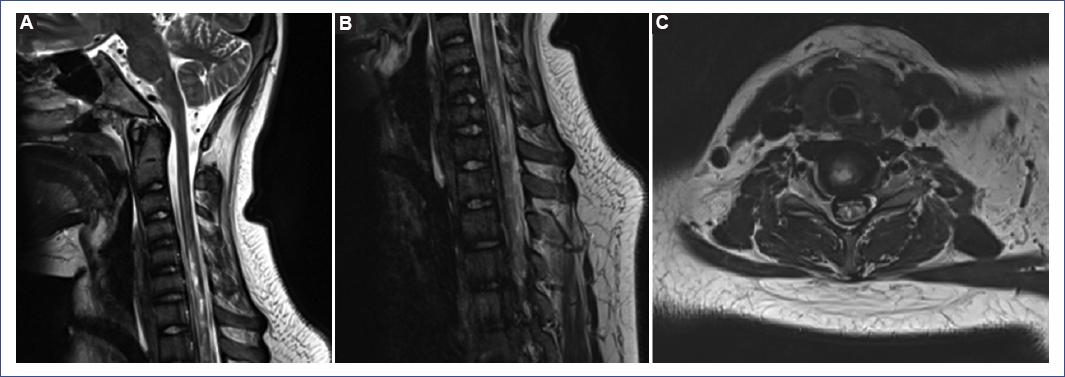

General laboratory tests were taken upon admission, with no pathological findings other than a positive SARS-CoV-2 real-time polymerase chain reaction by nasal swab. Head and spine computed tomography showed no alterations. Brain and spine magnetic resonance imaging (MRI) showed a hyperintense longitudinally extensive lesion from medullary levels C4 to T4 in the T2/STIR modality with discrete heterogeneous enhancement after the administration of contrast, with edema affecting the entire medullary cord in some regions and involvement of the gray matter at different levels, including anterior and posterior horns, mainly affecting the C7 medullary level, compatible with TM (Fig. 1).

Figure 1 Cervical-thoracic magnetic resonance imaging. A and B: T2-weighted sagittal images demonstrate a longitudinally extensive hyperintense signal extending from the C4 to T4 vertebral levels, compatible with transverse myelitis. C: T2-weighted axial image at the cervical level reveals a central hyperintense signal within the spinal cord.

We describe imaging results consistent with TM on MRI, including a hyperintense lesion in T2/STIR modality, longitudinally extensive, well-defined, and homogeneous from C4 to T4 medullary levels26.